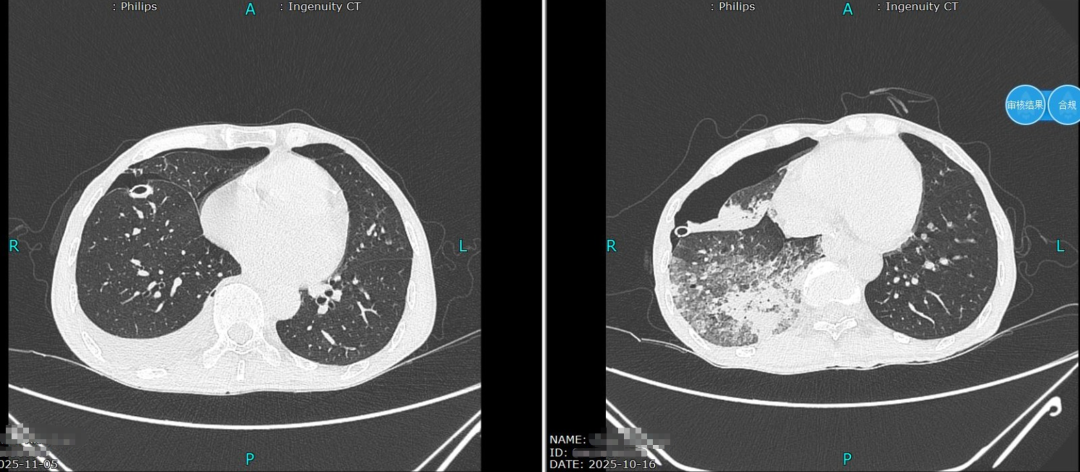

术后第9天复查胸部CT,显示肺组织完全复张,顺利拔除引流管;